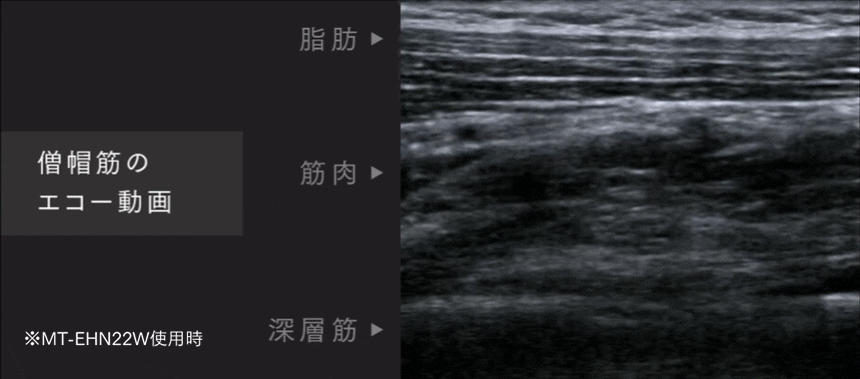

EVIDENCE

エコーによる検証動画

EMSで筋肉の奥深くまで動いています。

本当に低周波が奥深くまで届いているの?